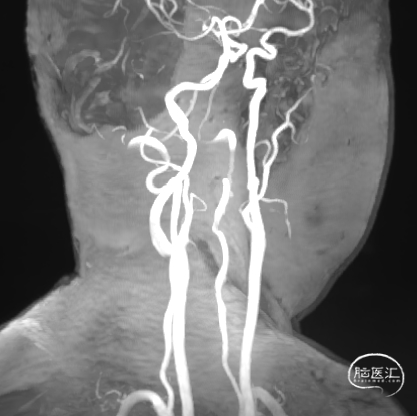

左侧椎动脉造影

![]()

右侧颈总造影:右侧大脑中动脉瘤

右侧椎动脉硬膜外V2、V3段梭形扩张,前向血流通畅。